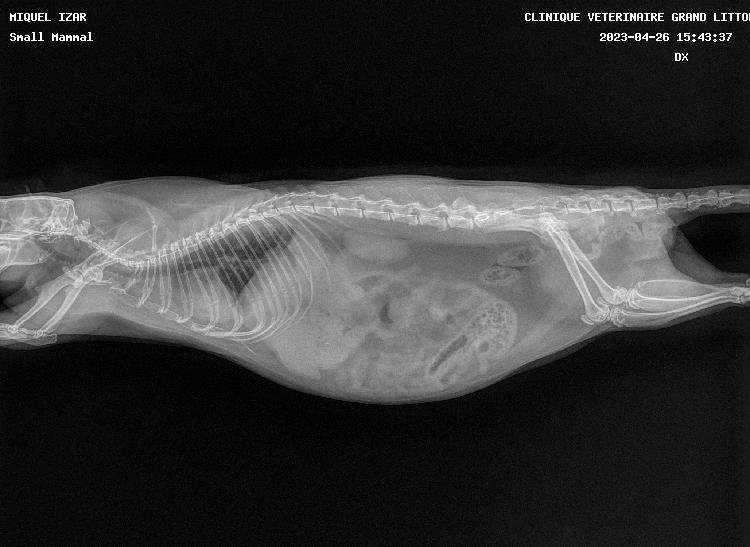

pas de super bonnes nouvelles car les deux miss ont les poumons atteints, si je m'en doutais un peu pour Izar qui ronflait depuis mars (c'est vite parti avec le collyre dans le nez) et respirait une peu trop vite, je suis tombée des nues pour Thari, qui me fait un coup à la Seren : zéro symptôme mais poumons pourris (si seulement elle pouvait avoir la même longévité :siffle:). Les deux pupuces sont donc sous deux antibiotiques (un par injection et un par voie orale) et Izar à en plus un AINS. Contrôle radio prévu dans quelques semaines.

Petites photos des belles et radios en spoil

Thari

Thariprofildroitavril2023.jpg.5c18040e016999d23a3866f24f5c81e8.jpg

Tharifaceavril2023.jpg.6759497e1a95d196154db5a6af44e844.jpg

Thariprofilgaucheavril2023.jpg.297630575b4261f43627592bdb11e17a.jpg